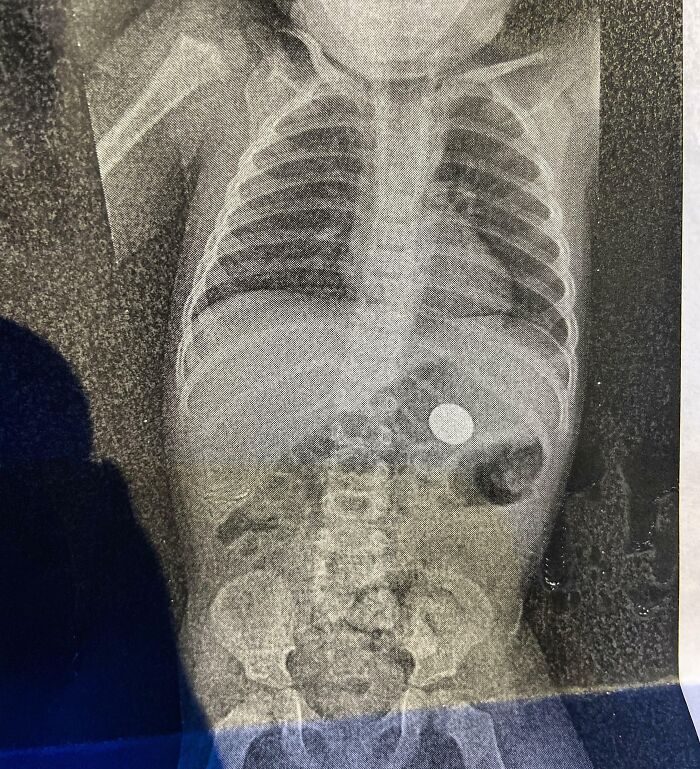

On Valentine's Day, My Son Decided To Show Me His First Magic Trick: How To Make A Coin Disappear. One X-Ray Later, I Found It

In other words, this entire tradition might be the figment of the imagination of a poet looking back at the older meanings of Valentine’s Day. So if you rank among the folks who had a big Valentine’s Day fail or you don’t like the holiday in general, perhaps it can help to recognize that the whole idea might be made up in the first place.